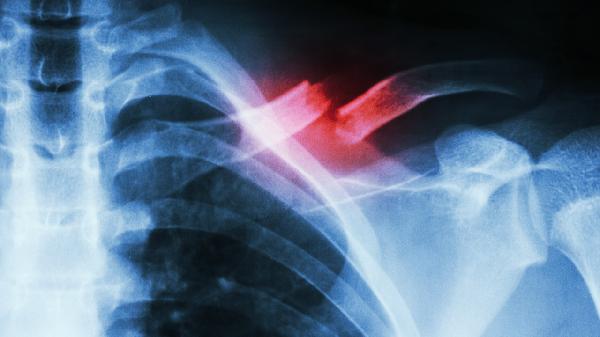

骨折线模糊是开始锻炼的基础指标,需通过X光确认骨痂形成。临床愈合通常需3-4周,此时可进行被动关节活动。完全负重训练需等待骨性愈合,约需8-12周。